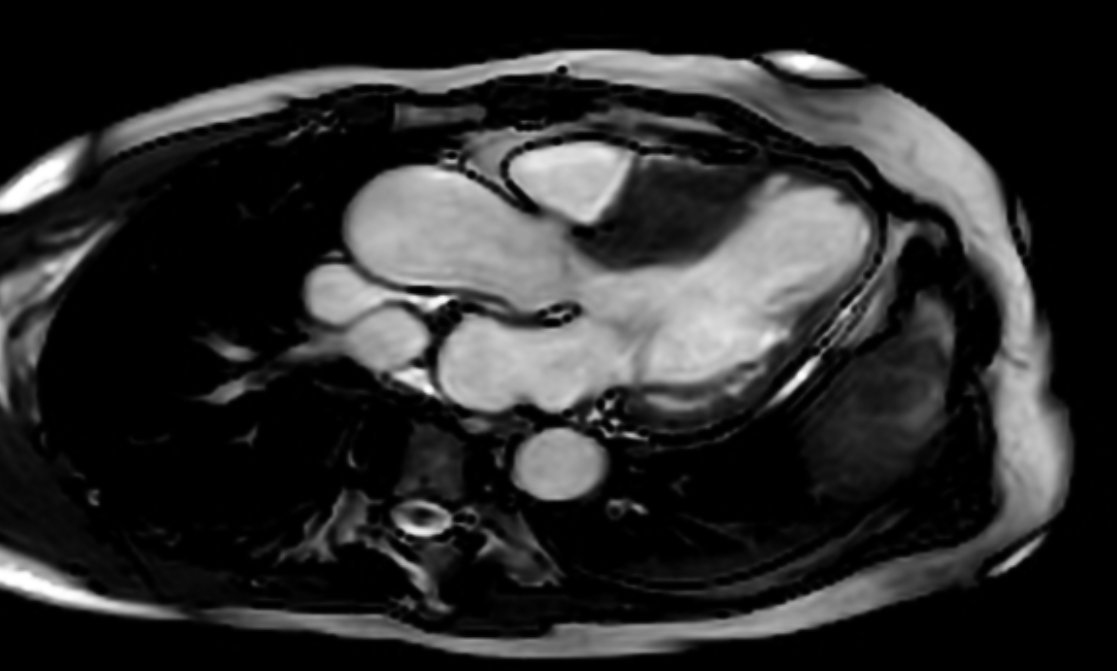

Clinical Case [Uncaptioned image] [Uncaptioned image]

Image Findings: The patient underwent contrast-enhanced computed tomography which showed features of a congested liver with flip-flop pattern of enhancement. Hepatic veins show hypoattenuation on delayed phase. An accessory hepatic vein is also noted in segment VI. A diagnosis of Budd Chiari syndrome (BCS) was made on the basis of the clinical and imaging features. The patient was referred to the interventional radiology team for an endovascular rescue. On conventional venogram, the diagnosis of BCS was confirmed as the hepatic veins were thrombosed. An accessory segment VI hepatic vein was noted draining into the IVC…